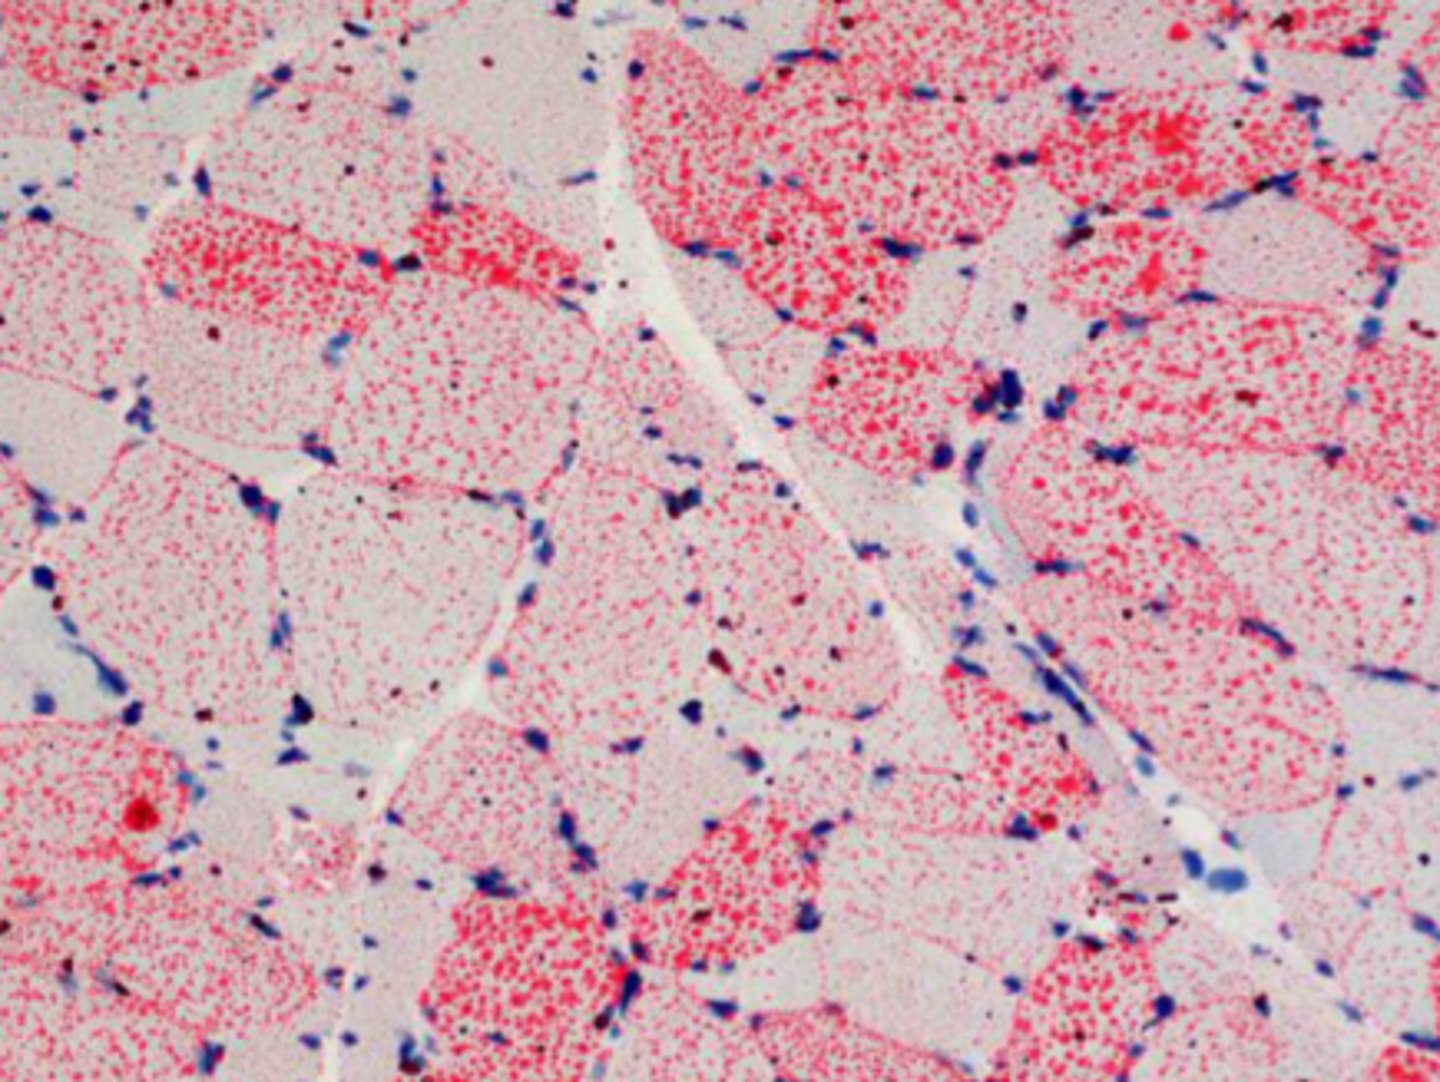

Identify the pathology?

EPSSM - Glycogen granules in muscle